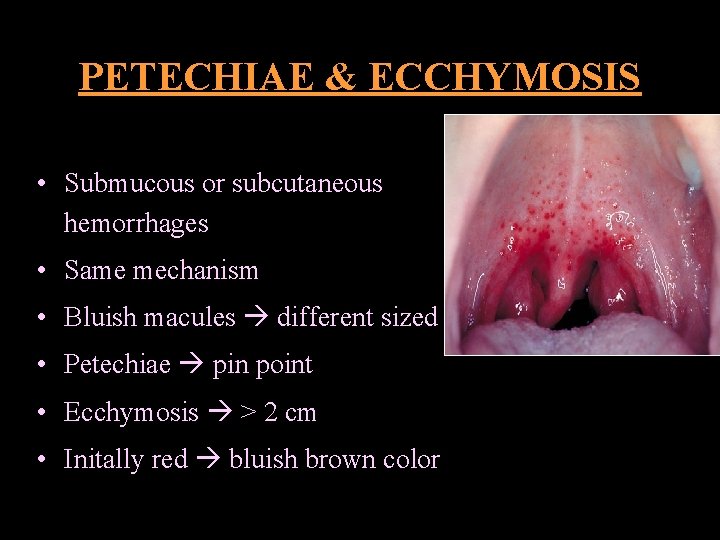

PETECHIAE & ECCHYMOSIS • Submucous or subcutaneous hemorrhages • Same mechanism • Bluish macules different sized • Petechiae pin point • Ecchymosis > 2 cm • Initally red bluish brown color